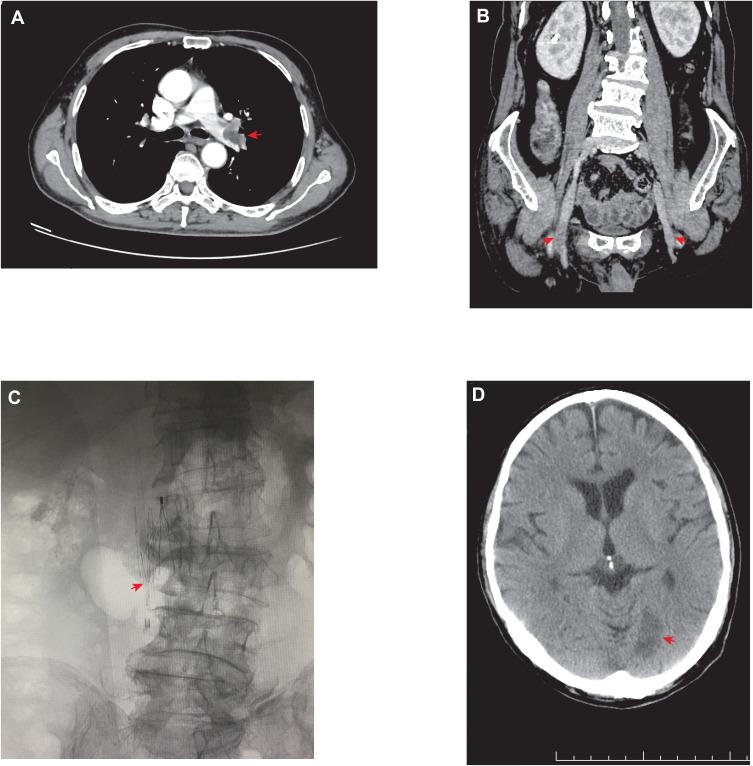

Immune checkpoint inhibitors may cause unique immune-related adverse events. Vascular thrombosis, especially arterial thrombosis, is rare but life-threatening, and little is known about its relevance to immunotherapy. Here, we reported two cases of vascular thrombosis, including venous and arterial thrombosis in cancer patients receiving anti-PD-1 antibody in combination with chemotherapy. Systemic corticosteroids and anticoagulant treatment were administered immediately in two cases. In case 1, anti-PD-1 antibody was permanently discontinued, and recurrence of vascular thrombosis was not observed during the follow-up. In case 2, the patient continued anti-PD-1 immunotherapy and unfortunately died of cerebral infarction 2 months later. This case report provides a strong evidence for the association between PD-1 blockade and vascular thrombosis and offers some general guidelines on the management of the immune-related vascular thrombosis events induced by anti-PD-1 therapy.

免疫检查点抑制剂可能会引发独特的免疫相关不良事件。血管血栓形成,尤其是动脉血栓形成,虽罕见但危及生命,而关于其与免疫治疗的相关性却知之甚少。在此,我们报告了两例血管血栓形成病例,包括接受抗PD - 1抗体联合化疗的癌症患者发生的静脉和动脉血栓形成。两例均立即给予全身性皮质类固醇和抗凝治疗。病例1中,抗PD - 1抗体被永久停用,随访期间未观察到血管血栓形成复发。病例2中,患者继续接受抗PD - 1免疫治疗,不幸的是2个月后死于脑梗死。本病例报告为PD - 1阻断与血管血栓形成之间的关联提供了有力证据,并为抗PD - 1治疗引起的免疫相关血管血栓形成事件的管理提供了一些通用指南。